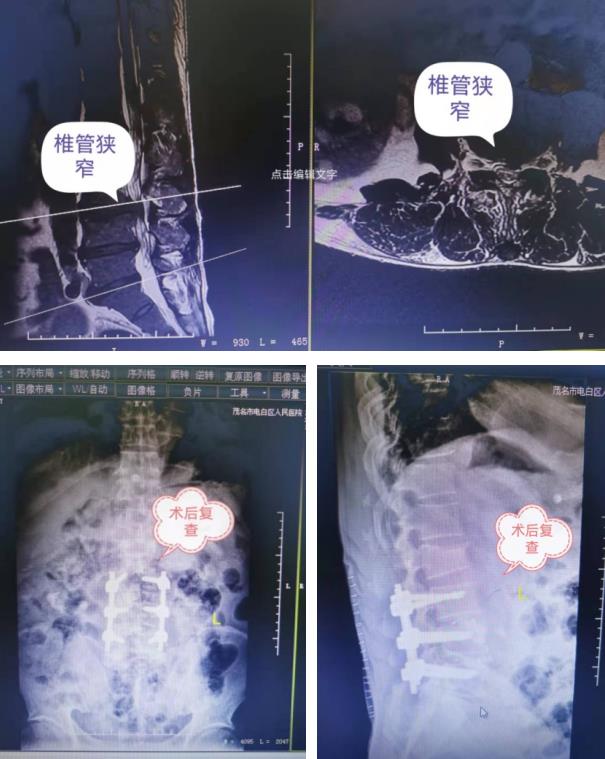

12月13日,骨外科王清富副院長(zhǎng)帶領(lǐng)骨外科團(tuán)隊(duì)與手術(shù)室醫(yī)護(hù)密切合作,為顏伯全麻下,采用改良型TILF手術(shù),成功實(shí)施了腰L3/4、L4/5椎管減壓、椎間融合、釘棒內(nèi)固定術(shù),既可徹底解除椎間盤(pán)突出對(duì)硬膜囊及神經(jīng)根的壓迫,又能保存腰椎的整體穩(wěn)定性,創(chuàng)傷小,出血小。

術(shù)后當(dāng)天,顏伯就感到腰痛及下肢疼痛基本消失了,夜晚也能睡個(gè)安穩(wěn)覺(jué)了。骨外科一區(qū)醫(yī)護(hù)團(tuán)隊(duì)后續(xù)會(huì)針對(duì)顏伯術(shù)后恢復(fù)情況,如期制定了康復(fù)計(jì)劃,并指導(dǎo)顏伯進(jìn)行功能鍛煉。